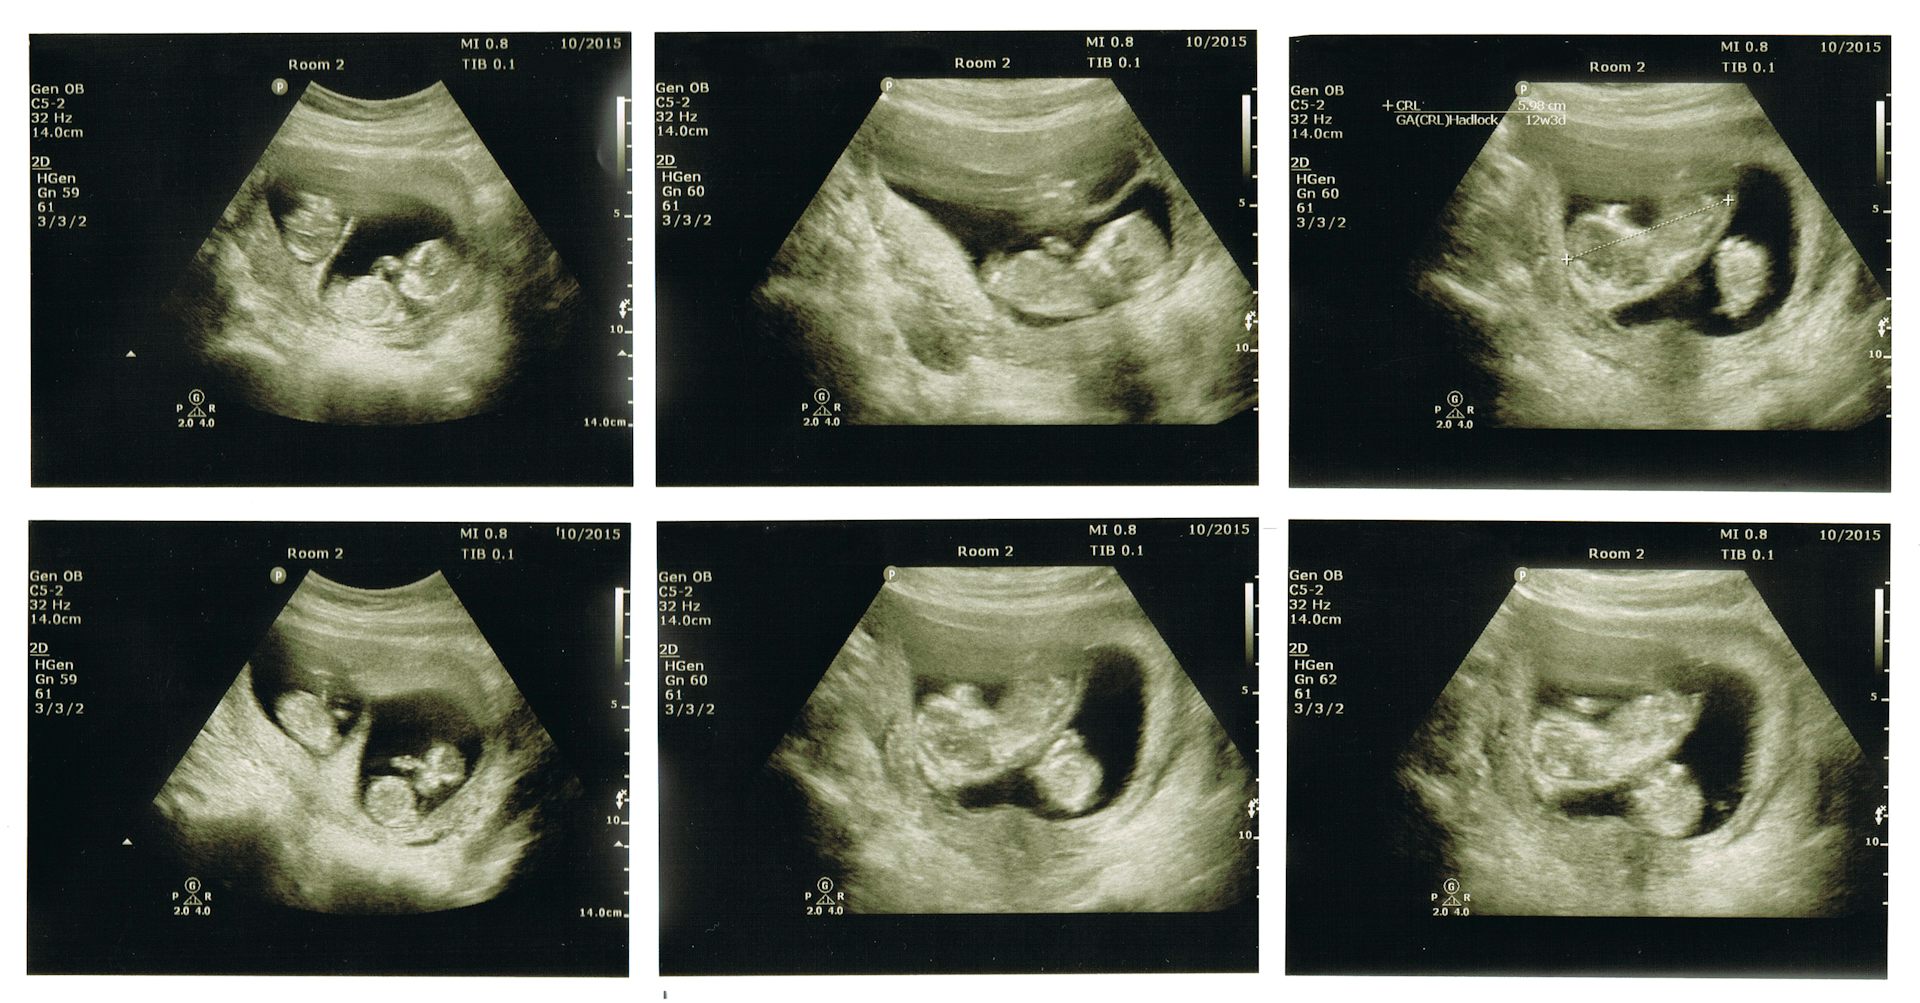

Возьмем, к примеру, УЗИ при беременности. Здесь каждая деталь на вес золота. Будущие родители хотят разглядеть каждую черточку лица своего малыша. В таких случаях специалисты могут использовать более высокое разрешение, достигающее 1024×768 пикселей. Это позволяет получить более детализированное изображение, не жертвуя при этом скоростью обработки данных.

А что насчет 3D и 4D УЗИ? Эти технологии произвели настоящую революцию в пренатальной диагностике. Они требуют еще большего объема данных. Размер таких изображений может достигать 1280×1024 пикселей и даже больше. Но стоит ли гнаться за гигантскими размерами? Не всегда. Важно помнить, что качество УЗИ фото зависит не только от количества пикселей.